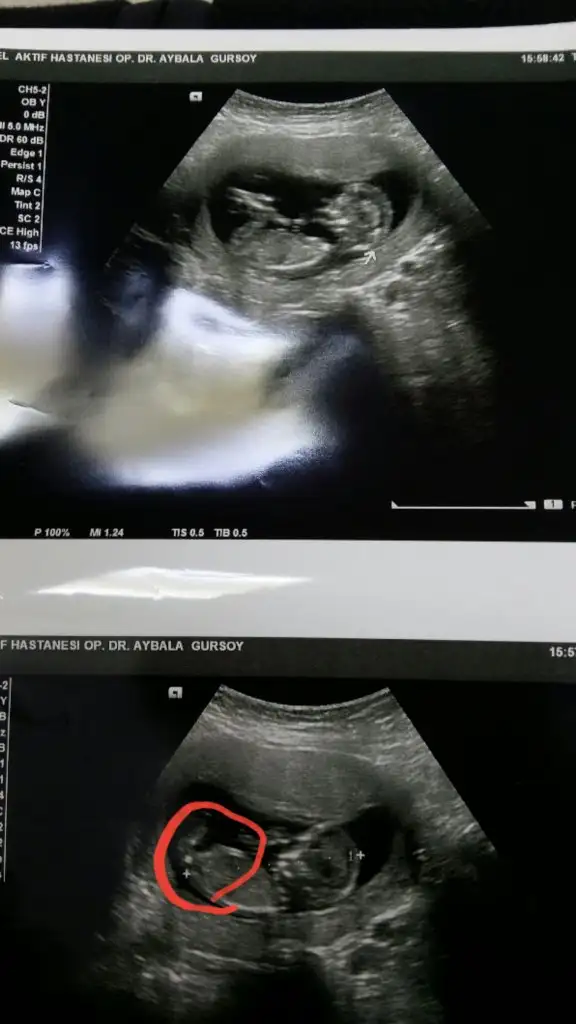

dr soylemeden siz gorun genital nub teorisi ( bebegin cinsiyeti)

Siz de yine bakarmısınız net söyledi kız diye herkes erkek demişti sizin gibi bende öyle diyordum ama ters köşe yaptı galiba bizimki çok hareketliydi 🤭🤣

ya kızlar bu resim bnim kaç gündür aklımı karstryo burda kız gibi doktor erkek dedi